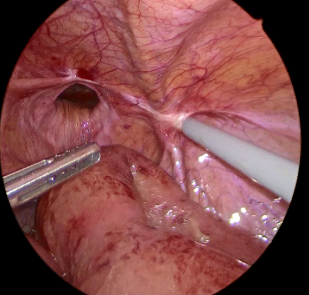

ソケイヘルニア(脱腸)の嵌頓では腸管(主に小腸)や内臓脂肪がヘルニア嚢内に脱出してヘルニア門に挟まれ元に戻らなくなった状態になります。

特に腸管の場合には、腸内の流れが遮断されて腸閉塞になる場合や腸管の血行が遮断されると腸管壊死を起こすことがあります。腸管を切除せざるを得ない場合には治療に時間を要する可能性があります。

腸管を温存できた場合も多くの場合、図のように嵌頓を解除した腸管にダメージを追っており、慎重な術後管理が必要となります。